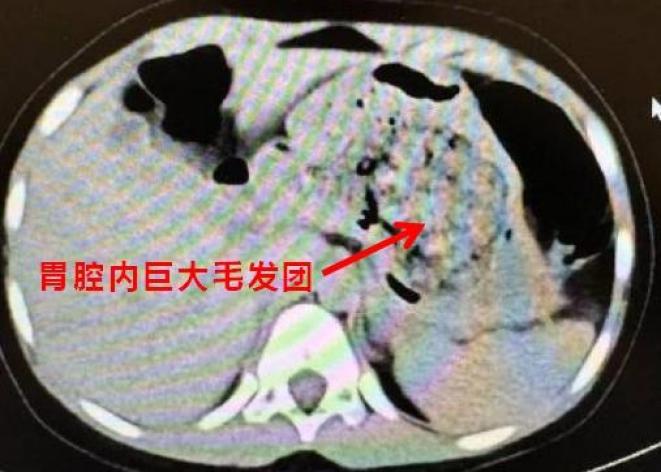

医生听到这里豁然开朗,原来在CT阅片的时候,发现了孩子胃里面有一团密度较高的团块,结合母亲提供的病史,医生断定孩子长期吃头发导致了胃内毛发成团,这也是这次腹痛的原因。

胃里巨大的毛发团花了3个多小时才把毛发取完

得出了初步诊断后,医生立即安排孩子住院,联系消化内科医生做胃镜检查,如果能够明确诊断,可以先尝试胃镜下取出,达到“无创”的效果。结果,当胃镜进入的瞬间,所有人都惊呆了,孩子胃内的毛发包裹食物残渣形成了一个巨大的团块,充满整个胃腔。